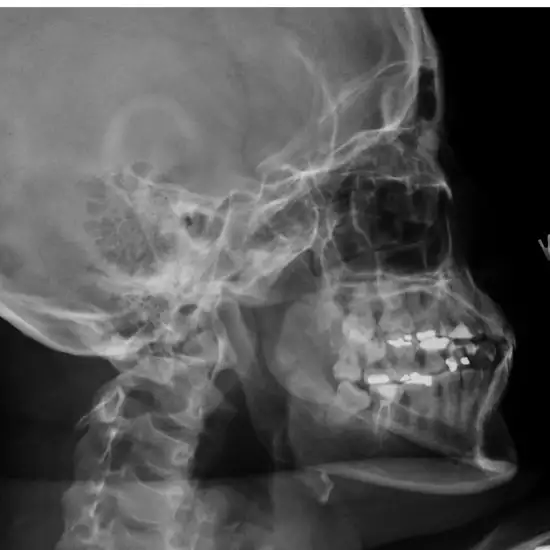

An X-ray of the temporomandibular joints is used to see the joint and the surrounding skin and muscles. The temporomandibular joint (TMJ) connects the mandible (jaw bone) and the skull.

To diagnose any suspected temporomandibular (TM) joint damage or fracture,

To identify suspected jaw dislocations.

To identify the cause of temporomandibular disorders, which may be caused by issues with the TM joint's muscles or the joint itself.